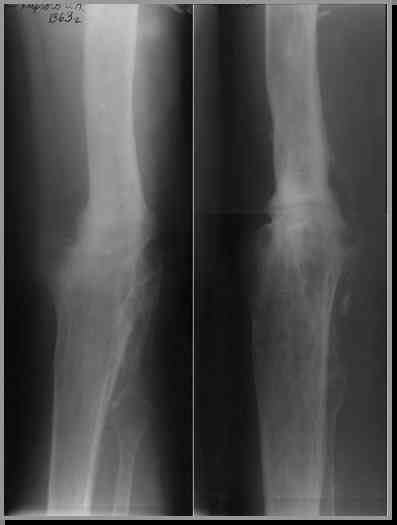

Через 4,5 лет после травмы выявлены рентгенологические признаки консолидации перелома, признаки хронического остеомиелита купировались. Аппарат был демонтирован. Пациент продолжил ходьбу с дозированной нагрузкой на конечность при помощи костылей. Через 2 месяца начал ходить при помощи трости. Однако, еще через 2 месяца отметил появление свищей на бедре с гнойным отделяемым и укорочение длины конечности. При осмотре в январе 2007 г.: пациент ходит при помощи костылей без опоры на левую нижнюю конечность, на бедре имеются множественные рубцы, на наружной поверхности сегмента в верхней и нижней третях имеются два свищевых хода со скудным серозно-гнойным отделяемым; отечности тканей конечности нет, пальпация безболезненная, отмечается укорочение длины конечности на 5 см, патологическая подвижность не определяется, имеется стойкая разгибательная контрактура коленного сустава (разгибание - 180 гр, сгибание - 170 гр), признаков нарушения кровоснабжения и иннервации тканей конечности нет. Температура тела нормальная. В общих анализах крови и мочи отклонений от нормы нет. [image 06,07, 08 (стрелками отмечены свищевые раны, 09, 10]Дорогие коллеги, я уверен, что у многих из вас после знакомства с данным клиническим наблюдением появится множество вопросов, касающихся уже проведенного лечения (особенно, сроков и способов). Сразу оговорюсь - я не смогу правильно ответить на многие вопросы (особенно касающиеся предшествующего периода лечения). Прошу вас, конечно по возможности, сосредоточить внимание не на разборе допущенных ошибок (проведенного лечения), а помочь добрым советом относительно тактики наших дальнейших действий. Наверное, кто-то располагает бесценным опытом лечения подобной патологии.